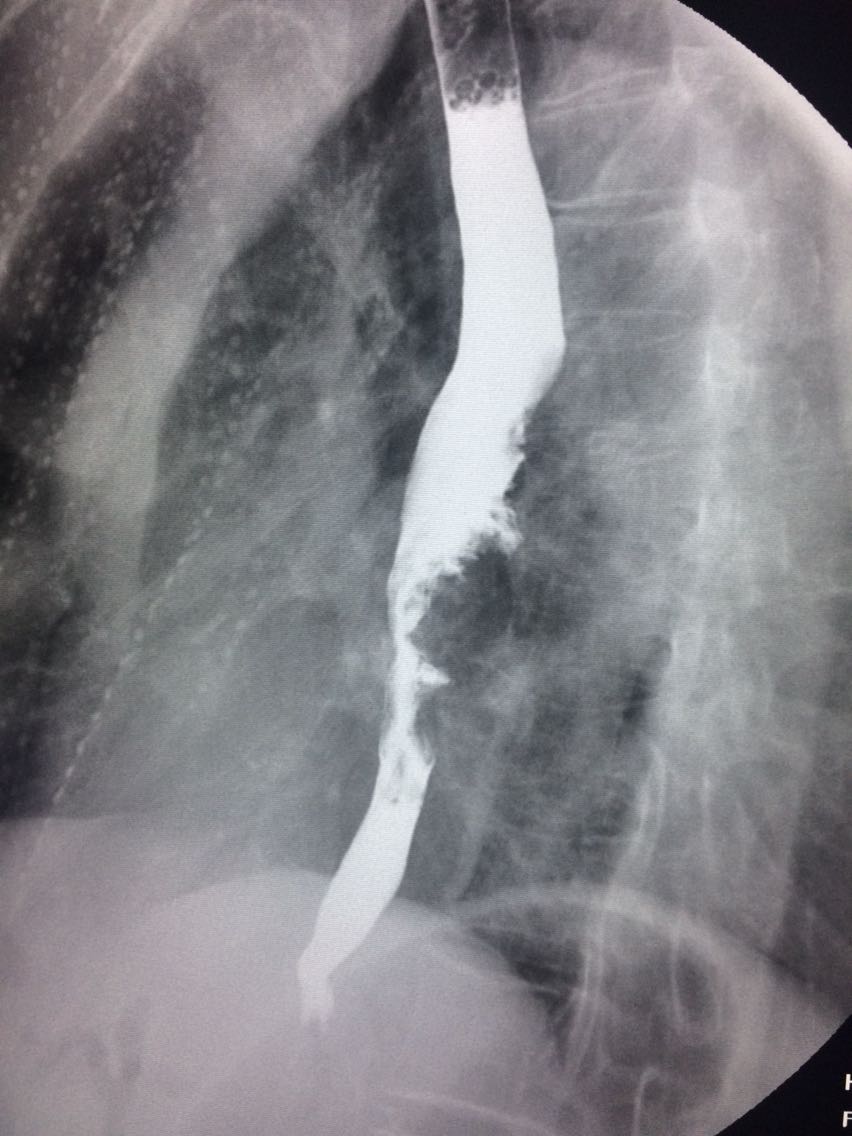

查体未见明显异常。 上消化道造影如图。

诊断食管癌。 造影剂逆流入胆道。